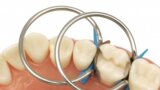

Predictable posterior restorations